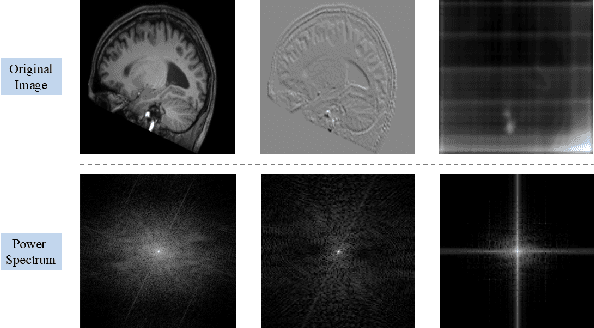

Abstract:We propose a Multifaceted Resilient Network(MRNet), a novel architecture developed for medical image-to-image translation that outperforms state-of-the-art methods in MRI-to-CT and MRI-to-MRI conversion. MRNet leverages the Segment Anything Model (SAM) to exploit frequency-based features to build a powerful method for advanced medical image transformation. The architecture extracts comprehensive multiscale features from diverse datasets using a powerful SAM image encoder and performs resolution-aware feature fusion that consistently integrates U-Net encoder outputs with SAM-derived features. This fusion optimizes the traditional U-Net skip connection while leveraging transformer-based contextual analysis. The translation is complemented by an innovative dual-mask configuration incorporating dynamic attention patterns and a specialized loss function designed to address regional mapping mismatches, preserving both the gross anatomy and tissue details. Extensive validation studies have shown that MRNet outperforms state-of-the-art architectures, particularly in maintaining anatomical fidelity and minimizing translation artifacts.